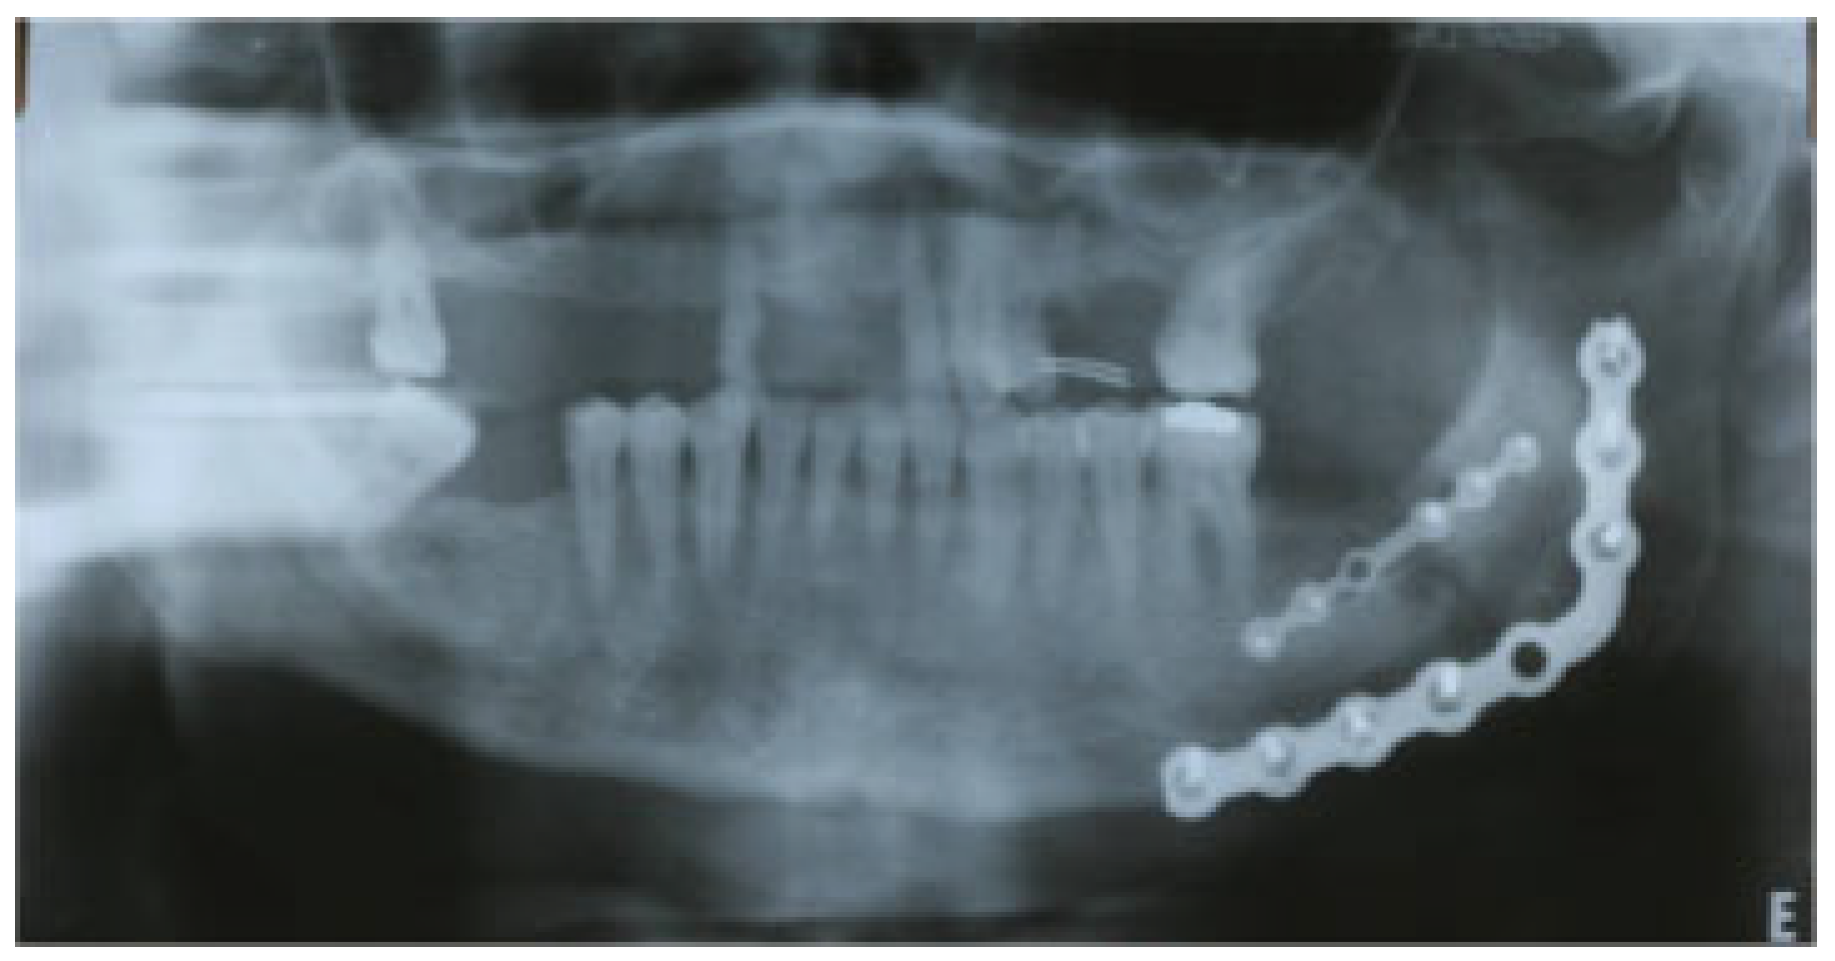

1.2. Case 2